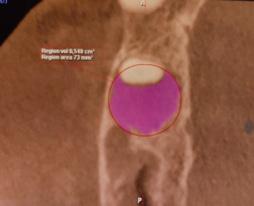

Aplicación de biomateriales post exeresis en un quiste inflamatorio radicular

Application of biomaterials post exeresis of a root inflammatory cyst

Javier Adrián Burgos, Renia Hurtado, Fabián Galindo, Juan Delgado....................................................97-106